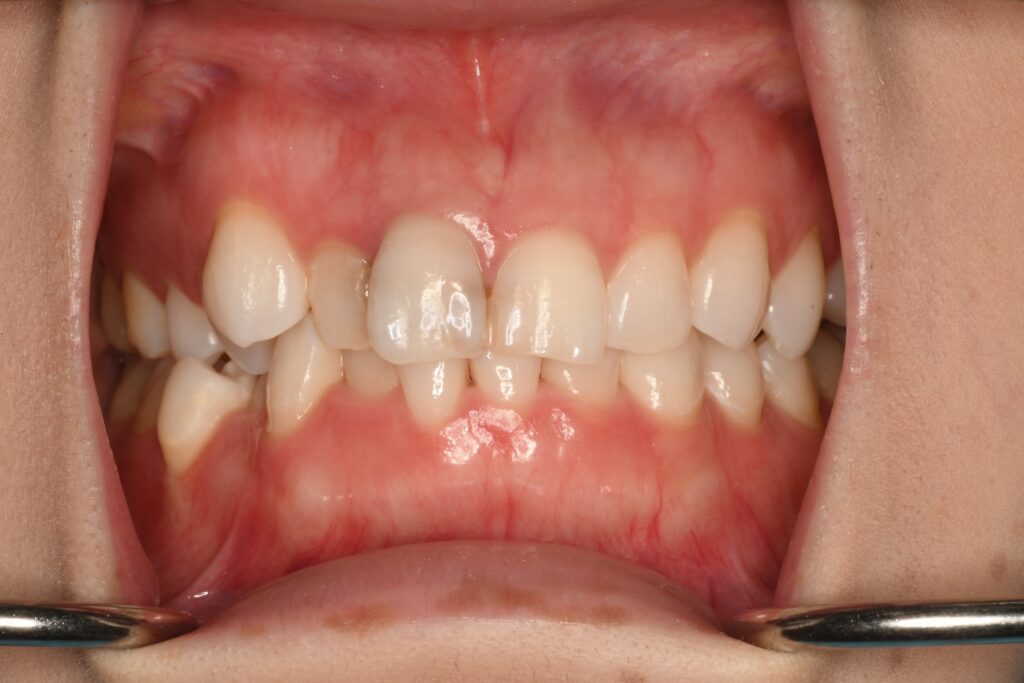

前歯が凸凹しているのが気になるなる20代女性のケース。今回に限らずですが、矯正治療の基本は隙間作りです。その隙間をどうやって作れるかが治療の分かれ道。方法論として、歯を抜く、歯と歯の間を形態修正する、奥歯を奥へ移動する。を一つあるいは複数選んで治療をします。どれを選べるかは、今の状態を知る必要があります。知るためには精密検査をします。

今回は検査をすると、骨格的に奥に隙間があるので奥歯を奥へ移動させて隙間を作る計画にしました。

歯のがたつきと噛み合わせが深いのが気になってましたが、費用の面で今まで矯正を先延ばしにしていました。もりや歯科さんに伺う前に、別の歯科のカウンセリングを受けましたが、ワイヤー矯正を勧められ、上下左右の前から4番目の歯を合計4本抜歯が必要と言われました。ですが、どうしてもワイヤーを装着するのが嫌で躊躇していました。

友人がもりや歯科さんでインビザライン矯正をしたとのことで、紹介していただきました。カウンセリングでは現在の歯の状況などを丁寧に説明していただきました。検査の結果、親知らずの抜歯のみでインビザラインでの矯正が可能とわかり、費用の面でも思っていたよりお安くできるとのことでこちらで矯正をすることに決めました。